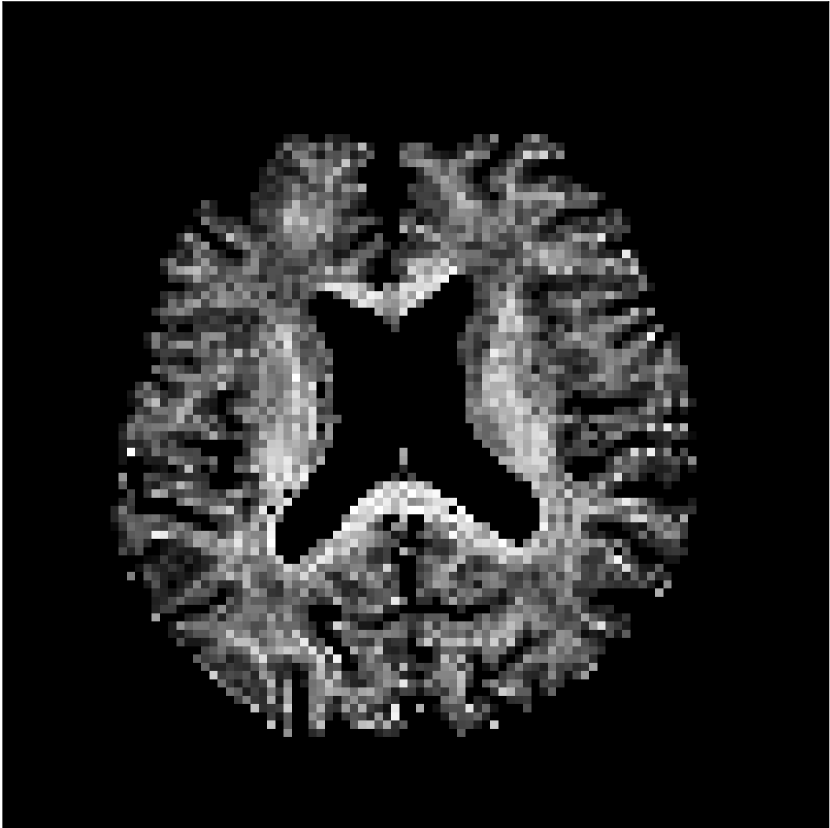

Figure 10 compares mean diffusivity maps across various partial Fourier factors between the CCNN and state-of-the-art methods.

No PF

7/8 PF

6/8 PF

5/8 PF

SoA

MD, m2/ms

CCNN

The methods perform similarly without partial Fourier acceleration, but as partial Fourier acceleration increases, the image is continually degraded in the SoA method, with "black voxels" appearing around the lateral ventricles. The CCNN method mitigates the appearance of these artifacts in the parameter maps.